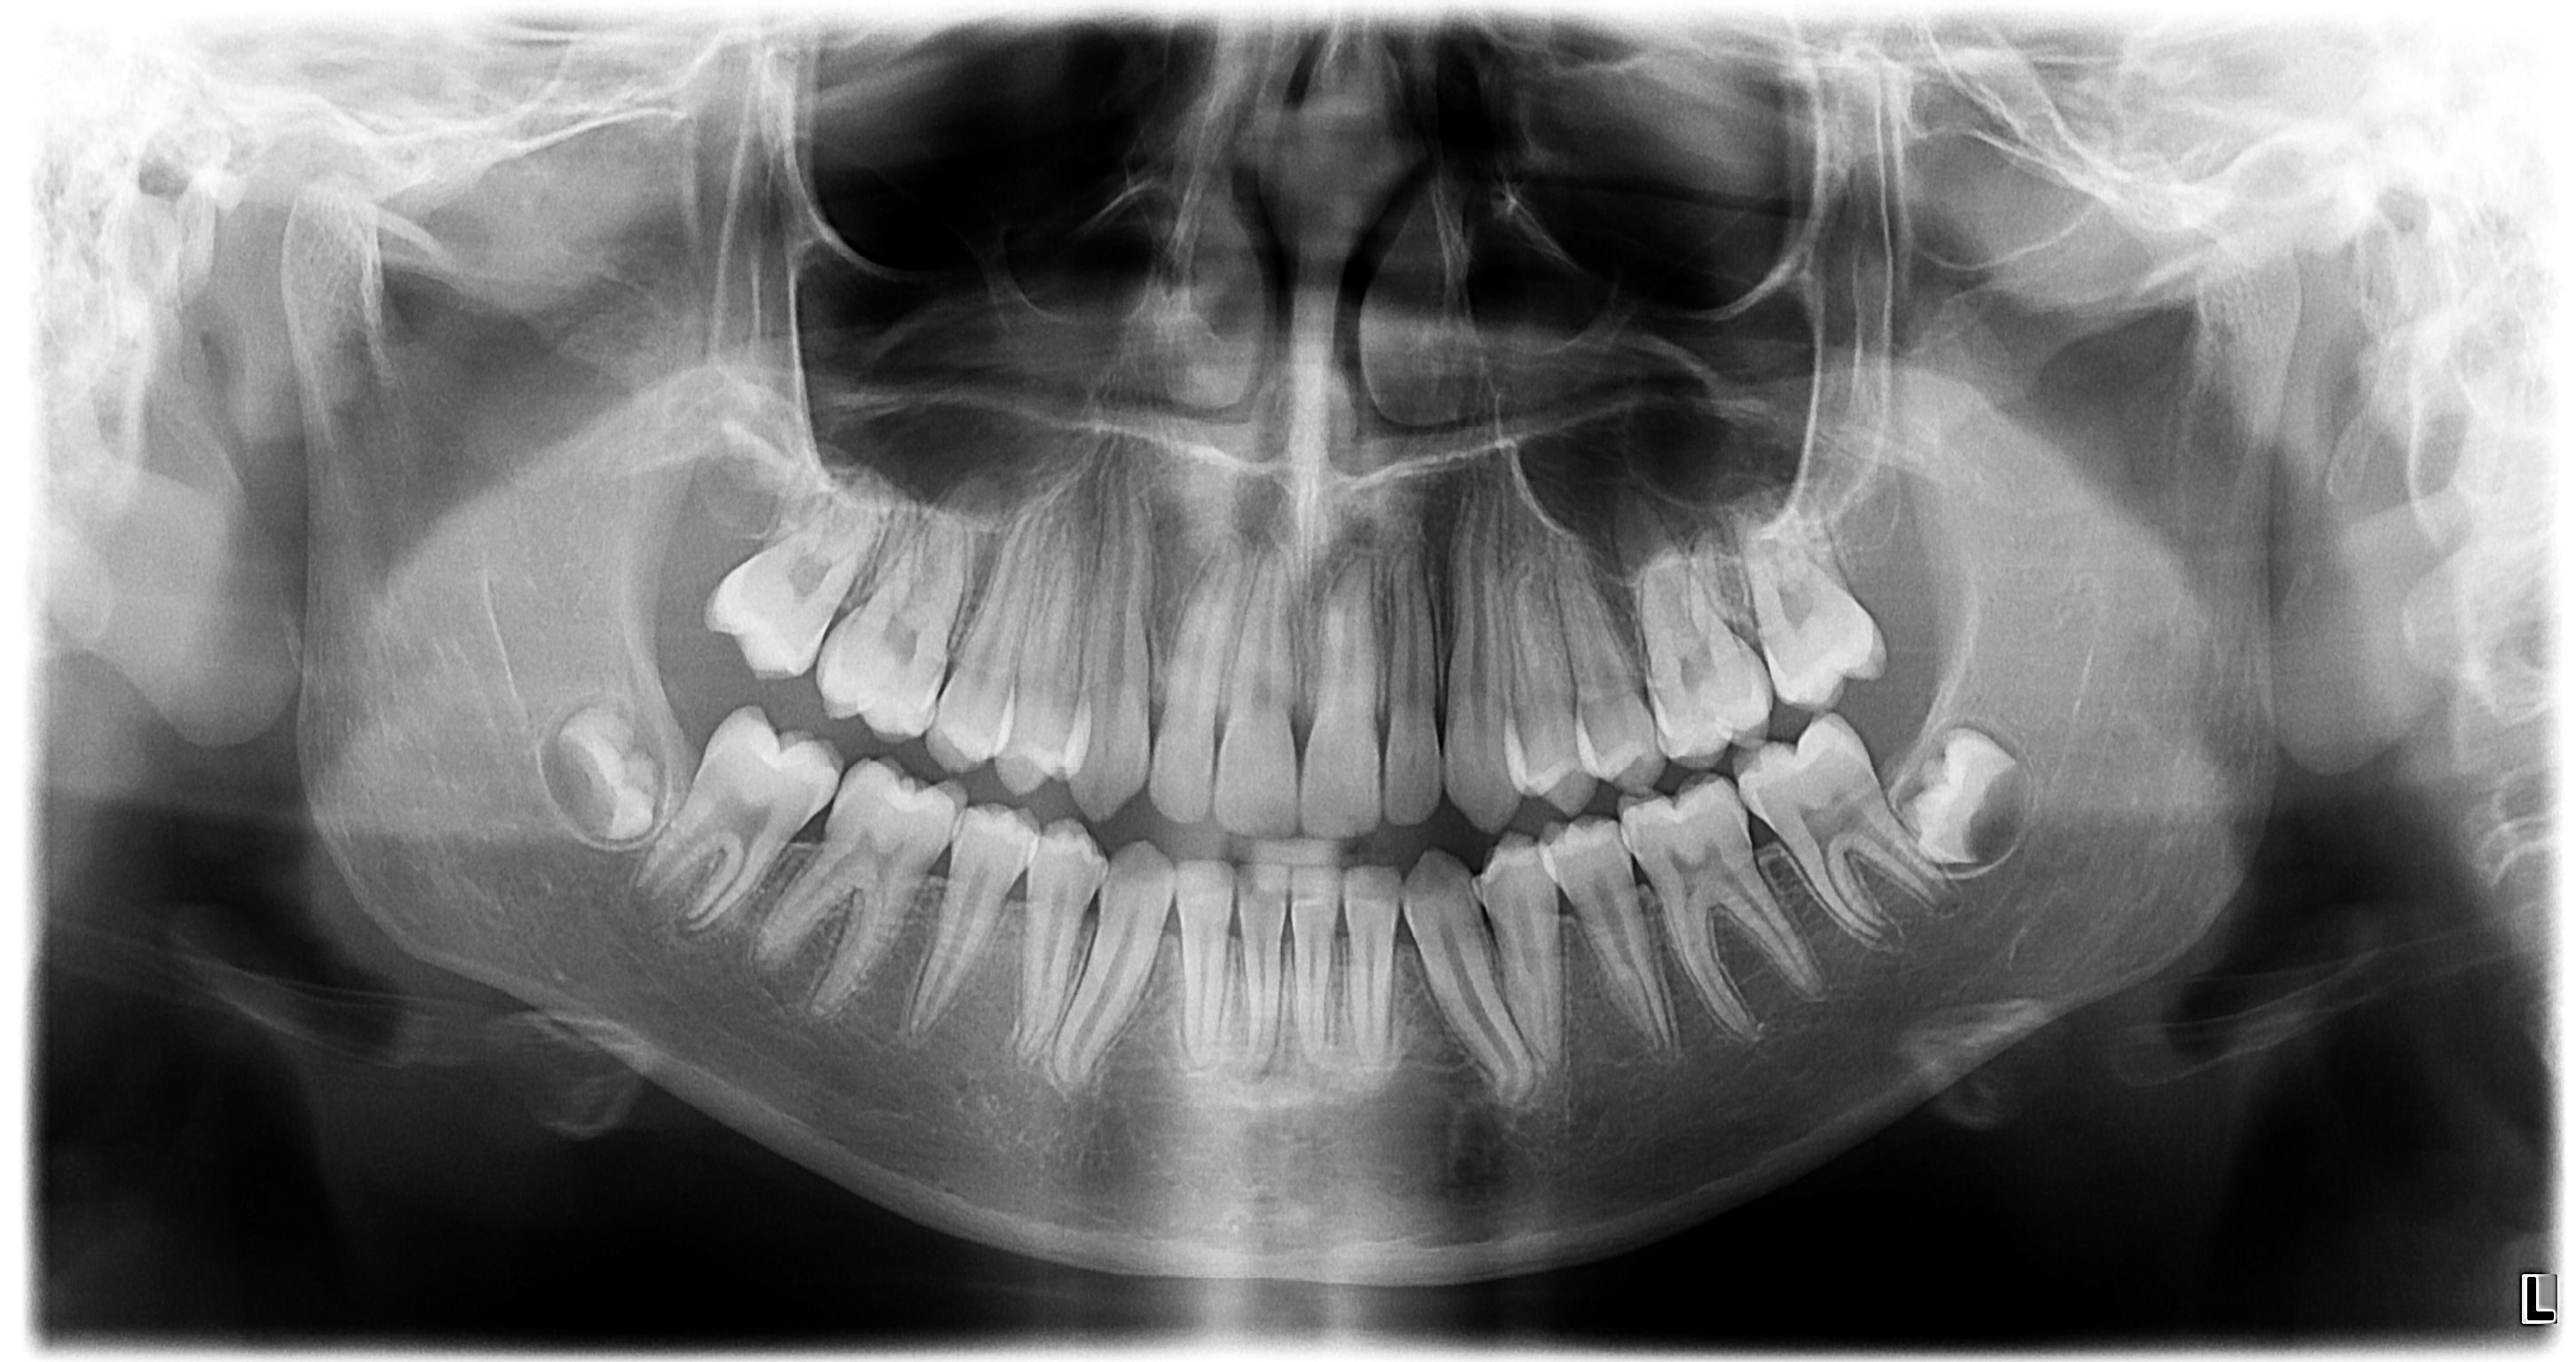

オルソパントモグラフ OP3D、ディゴラオプティメe、DTX Studio Clinic

当院には正確で安全な治療を行うための検査機器をとして、最新鋭の歯科用CTシステムを導入しております。このシステムは、低い被ばく線量(総合病院などの医科用CTの1/10以下)で、3次元データの情報を得ることができ、これまでのレントゲン検査の診断が難しかった部分の診断も行えます。これにより患者さんのへのわかりやすい説明と更なる治療成績の向上が見込めます。